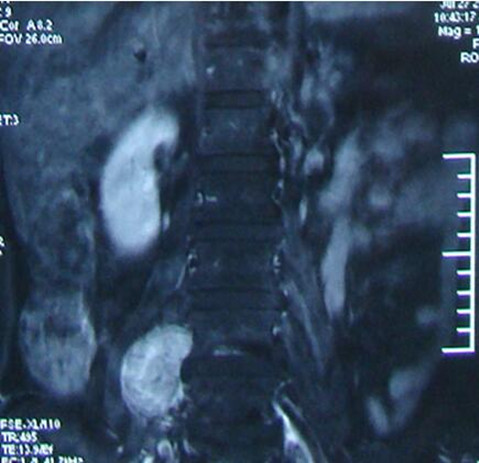

吴先生65岁,两年前无明显诱因出现双下肢麻木的症状,自行口服药物治疗无明显效果。入院前双下肢略肿胀。吴先生及家人慕名来我院就诊,行MRI检查示:“T3椎体水平脊髓内占位。”入院后查体及辅助检后,临床诊断为:脊髓占位性病变、颈椎病。于4月8日行脊髓探查、病变切除术。目前,吴先生切口愈合良好,肢体活动自如,生活完全自理。

手术难度:因患者为脊髓占位性病变,故手术需切开硬膜囊,探查脊髓,术中操作必须谨慎,若损伤脊髓可导致该节段以下的肢体运动、感觉障碍或瘫痪,若损伤神经根可导致单侧肢体运动、感觉障碍或丧失,需术中积极保护脊髓及神经根,手术风险极大。

术前胸椎MRI